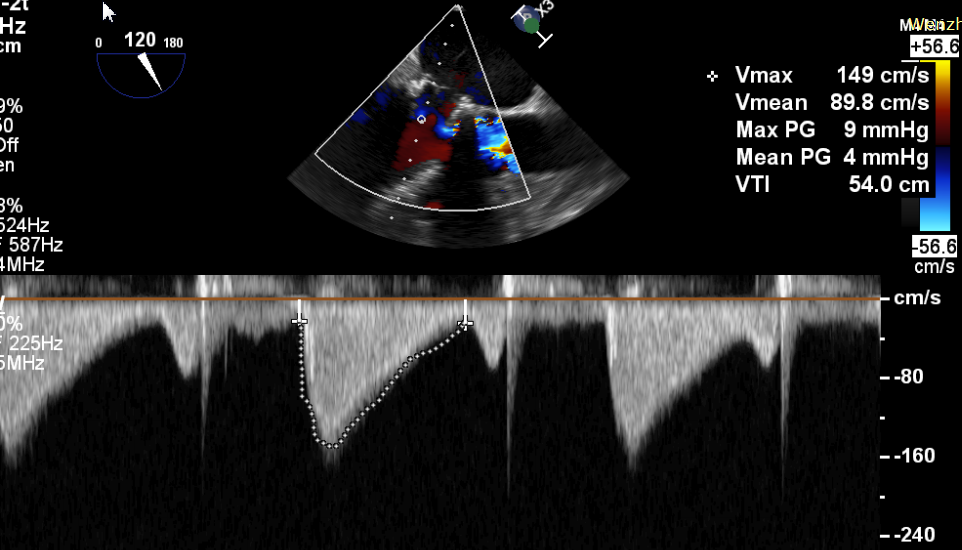

CDFI提示过瓣血流通畅

CDFI示少量瓣周漏

收缩期未见瓣周漏

左房内未见对比剂显影